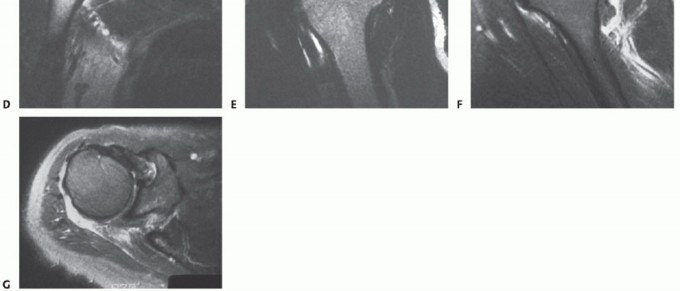

FIG 1 • A,B. Type III acromion, the so-called hooked acromion, on the outlet and AP views. C. Arthrogram confirming the presence of a rotator cuff tear with dye in the glenohumeral joint and the subacromial bursa simultaneously. D. T2-weighted coronal MRI showing cuff tear and its lateral to medial extent. E. T2-weighted sagittal oblique MRI showing the AP extent of the cuff defect. F. Another T2 sagittal oblique MRI showing the tear involving the teres minor but not the subscapularis. G. Axial T2 MRI of the same tear showing rupture of the teres minor with an intact subscapularis.

Standard radiographs, including anteroposterior (AP) views in internal and external rotation, an axillary view,

and an outlet view, should always be taken to look for the type of acromion (

FIG 1A

), acromioclavicular joint changes, and narrowing of the acromial-humeral interval (

FIG 1B

) and to rule out other conditions.

Additional preoperative studies include MRI, ultrasound, or arthrography.

Arthrography once was the gold standard but now is used only under rare circumstances (ie, when an MRI cannot be done). It can show a full-thickness cuff tear (

FIG 1C

) but requires an intra-articular injection with fluoroscopy and radiography.

The most commonly used study is an MRI. It not only shows the integrity of the tendons but also provides a three-dimensional view of the cuff (

FIG 1D-G

). This capacity makes the MRI a versatile preoperative planning tool.